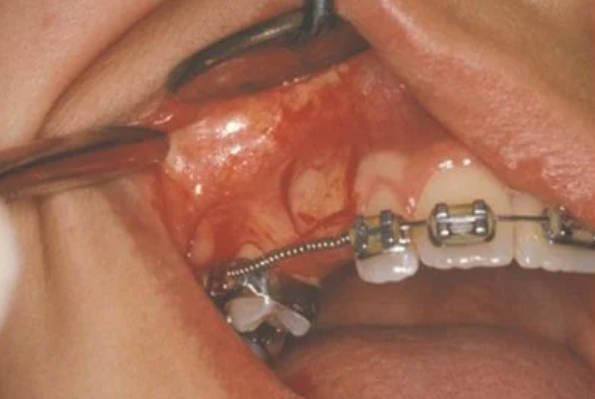

In cases where the eyeteeth will not erupt spontaneously, the orthodontist and oral surgeon will work together to get these teeth to erupt. Each case must be evaluated on an individual basis, but treatment will usually involve a combined effort between the orthodontist and the oral surgeon. The oral surgeon will expose and bracket the impacted eyetooth.

The goal is to erupt the impacted tooth and not to extract it. Once the tooth has moved into its final position, the gum around it will be evaluated. In some circumstances, there may be some minor “gum surgery” required.

The surgery to expose and bracket an impacted tooth is a very straightforward surgical procedure that is performed in the oral surgeon’s office. For most patients, it is performed using laughing gas and local anesthesia. In selected cases it will be performed under IV sedation if the patient desires to be asleep, but this is generally not necessary for this procedure. If the procedure only requires exposing the tooth with no bracketing, the time required will be shortened by about one half. These issues will be discussed in detail at your preoperative consultation with your doctor.